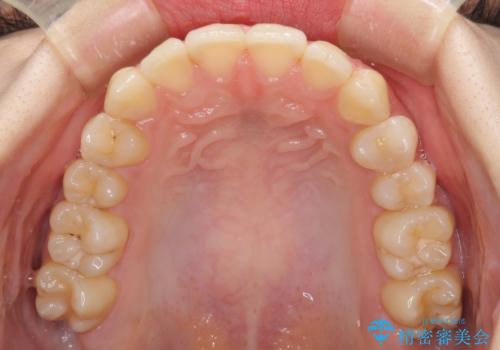

- 上下前歯のデコボコを気にして来院された患者様です。

以前矯正をした後戻りということで、歯列不正はそれほど大きくなかったため、インビザライン・ライトを用いて矯正治療を行うこととしました。

前歯のデコボコが残っており、シミュレーション通りに動いていない部分がありましたが、再矯正であることやご本人の満足いくところまでデコボコが改善されたとのことで、治療を終了することとしました。